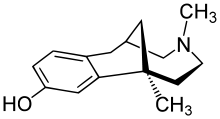

Morphinans

Morphinan series

- 3-Hydroxymorphinan

- 4-Chlorophenylpyridomorphinan

- Cyclorphan

- Levargorphan

- Levorphanol

- Levophenacylmorphan

- Levomethorphan

- Methorphan (racemethorphan)

- Morphanol (racemorphanol)

- Norlevorphanol

- N-Methylmorphinan

- Oxilorphan

- Phenomorphan

- Proxorphan

- Ro4-1539

- Stephodeline Xorphanol

Structures

| Other morphinans | ||||

|---|---|---|---|---|

4-chlorophenylpyridomorphinan 4-chlorophenylpyridomorphinan |

Cyclorphan Cyclorphan |

Dextrallorphan Dextrallorphan |

Levargorphan Levargorphan |

Levophenacylmorphan Levophenacylmorphan |

Levomethorphan Levomethorphan |

Norlevorphanol Norlevorphanol |

N-Methylmorphinan N-Methylmorphinan |

Oxilorphan Oxilorphan |

Phenomorphan Phenomorphan |

Dextromethorphan Dextromethorphan  levomethorphan levomethorphan |

Morphanol Morphanol |

Ro4-1539 Ro4-1539 |

Stephodeline Stephodeline |

Xorphanol Xorphanol |